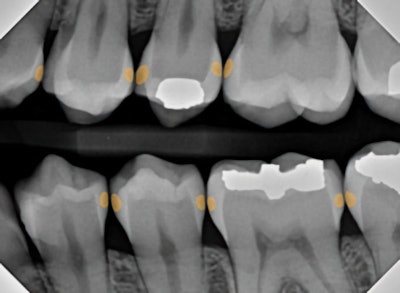

The first diagnostic innovation is AI-supported radiographic interpretation

Rather than the discernment of various shades of gray resting on the shoulders of the clinician, who may or may not have adequate time in every different clinical scenario, decay is highlighted by the computer AI software itself, making it a bit more difficult to miss a lesion and highly documenting the degree of enamel or dentin penetration of the lesion.

Figure 4: Traditional bitewing radiography indicates clear decay on tooth #13, with some evidence of incipient lesions on #s 12, 14, 18, 19, 20, and 21. It is quite possible for me to miss one or more of these lesions on the lower teeth during busy times at the office.Figure 4: Traditional bitewing radiography indicates clear decay on tooth #13, with some evidence of incipient lesions on #s 12, 14, 18, 19, 20, and 21. It is quite possible for me to miss one or more of these lesions on the lower teeth during busy times at the office.

Figure 5: AI radiographic interpretation helps highlight lesions and provides insight as to the extent of the decay.Figure 5: AI radiographic interpretation helps highlight lesions and provides insight as to the extent of the decay.